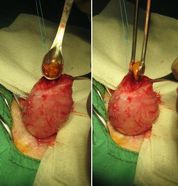

| お腹を開いて、膀胱を取りだした状態です。 |

専用の器具を使い、結石を取り出しています。 |

| 取り出した結石です。 のちに、検査センターで成分の分析をし、再発しないように療養食の指導をしています。 |